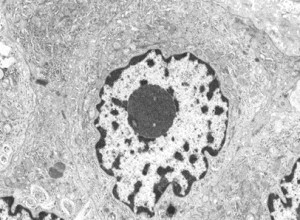

Electron Microscope Image of Malignant Mesothelioma<br />Nucleolus is clear

Malignant mesothelioma cells in pleural fluid

It can be difficult to differentiate malignant mesothelioma from adenocarcinoma cells or reactive mesothelial cells in body fluids. Therefore, we would like to examine the differentiation between adenocarcinoma cells and malignant mesothelioma cells appearing in body fluids using immunohistology, electron microscopy, and fluorescence in situ hybridization.

Differentiation of Malignant Mesothelioma from Adenocarcinoma Cells Appearing in Body Fluid -Using Immunohistology and Electron Microscopy